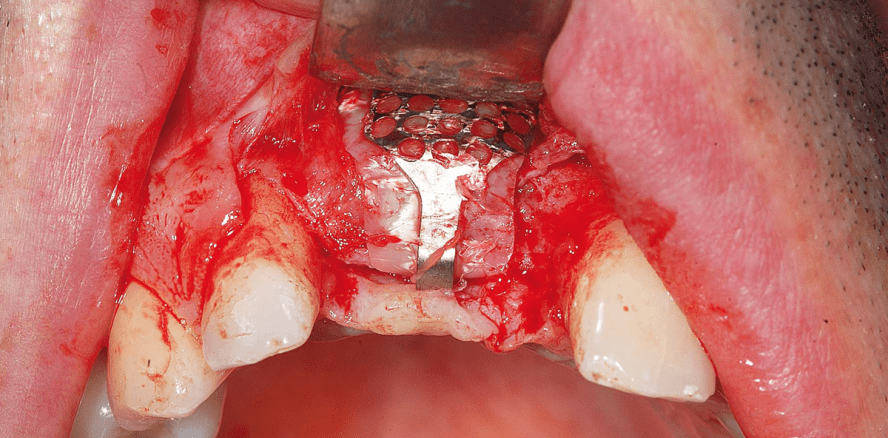

Es wurde ein Mukoperiostlappen mit Entlastungsinzisionen gebildet, wodurch ein großer vertikaler Defekt sichtbar wurde (Abb. 2). Ein Implantat (Neoss ProActive® Straight) wurde bei dem 8 mm vertikalen Defekt gesetzt (Abb. 3). Autogene Knochenzylinder (3,4 x 4–5 mm) wurden aus der Linea obliqua des Unterkiefers in der Molarenregion entnommen und um das Implantat eingebracht, um die Regeneration zu beschleunigen und als Platzfüller zu fungieren (Abb. 4). Vom gleichen Hersteller wurde eine titanverstärkte Membran zugeschnitten, geformt und in den OP-Situs eingepasst sowie bukkal mit zwei Stiften fixiert (Abb. 5). Die Weichgewebeseite der Membran verfügt über eine dichte Textur, welche die Interaktion mit dem Weichgewebe fördert. Dies verleiht der Membran Stabilität und bildet eine Barrierefunktion, sodass das Risiko einer Infektion bei Membranfreilegung minimiert wird. Die Hartgewebeseite verfügt über eine expandierte Textur, die eine vorhersagbare Hartgewebeintegration ermöglicht. Zusammen mit der starren Netzkonfiguration kann eine vollständige Knochenauffüllung erreicht werden. Ein spannungsfreier Lappenverschluss wurde durch Entlastung des Periosts auf der bukkalen Seite erreicht (Abb. 6). Die Weichgewebeheilung verlief komplikationslos (Abb. 7 und 8).